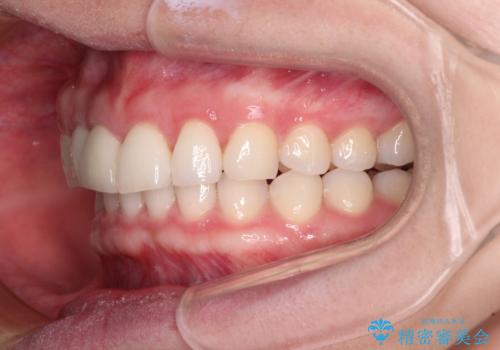

治療前、下顎前歯はほとんど見えない咬み合わせでしたが、矯正治療によりディープバイトが改善されました。

矯正治療中に前歯2本のクラウンは外れてしまい、途中仮歯に替える必要があったので期間は掛かりましたが、歯列も整い、負担のかからない咬み合わせを達成することができました。